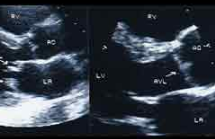

Ventricular Tachycardia

Janet Poponick, MD; Katherine Landen, MD; Kristen Schmidt, MD

<p><img src="/sites/default/files/old/img_4db9715d84d34.jpg" alt="Figure" width="150" height="150" style="float: left; margin-left: 8px; margin-right:...